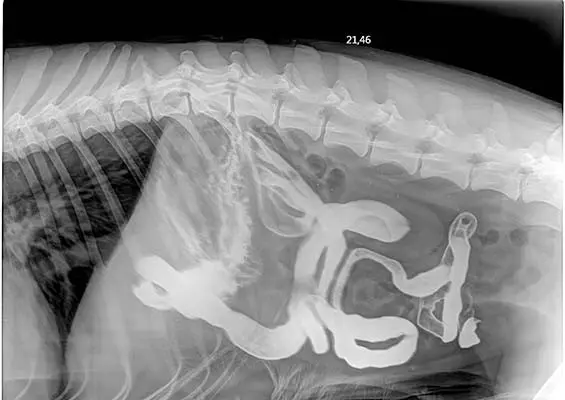

Dlaczego warto wykonywać dodatkowe badania obrazowe w diagnozowaniu chorób przewodu pokarmowego?